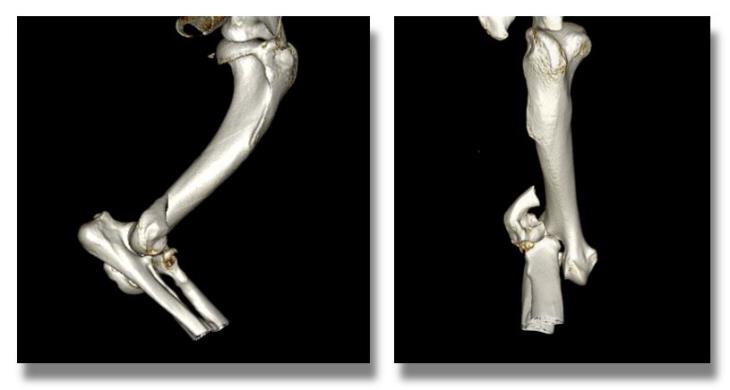

A CT scan of the affected limb was obtained to allow for preoperative planning and to rule out additional fissures that might have gone undetected on plain radiography.

In order to obtain a strong and reliable repair, internal fixation with a transcondylar screw and an orthopaedic plate and screws was chosen.

Up until recently, the standard way of treating such fractures would have involved the use of plates that are contoured to the patient’s bone shape at the time of surgery. This can be a time-consuming procedure which prolongs the duration of the anaesthetic. Furthermore, bending a metal plate to the desired shape increases the risk of implant failure due to the formation of micro-fissures within the metal itself.

To overcome these limitations, a team of Orthopaedic Specialists and Biomechanicals at Fusion Implants has developed an implant that precisely replicates the shape of the surface of the lateral part of the humeral condyle and thus does not require additional contouring in most cases.

Eastcott Referrals is proud to have been chosen as one of the first few centres in the UK to use this novel implant known as the Lateral Epicondylar Anatomical Plate (LEAP).